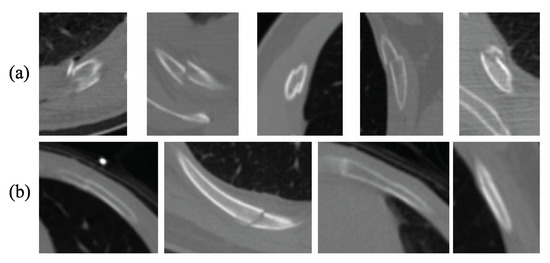

4.1.1. Datasets